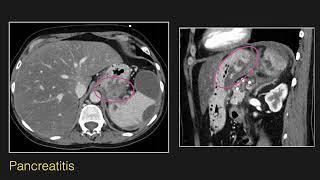

Abdominal Radiology Lecture: CT of Esophageal and Gastric Pathology

Abdominal Radiology Lecture: CT of Esophageal and Gastric Pathology

Learn Abdominal Radiology